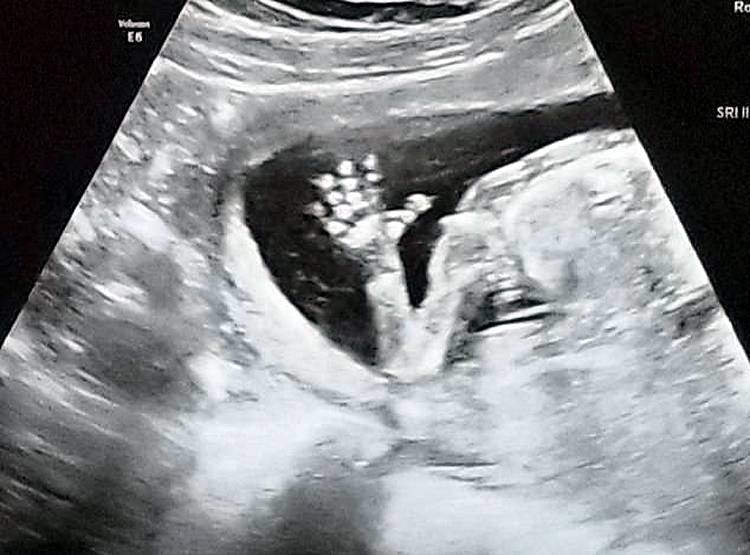

बिथैनी ने बताया कि मैं पूरे गर्भवस्था के दौरान डरी हुई थी कि पता नहीं मेरे इलाके में कोई ऐसा डॉक्टर है जो मेरे दो-दो अंगों के साथ मुझे डिलीवरी करा सके. मुझे यहां के डॉक्टरों पर तब भरोसा हुआ जब मैंने 9 हफ्ते के बाद अपनी बच्ची का हार्टबीट सुना.  (फोटोः बिथैनी मैक्मिलन)